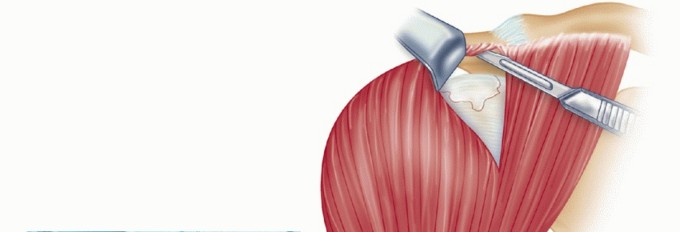

When the cuff cannot be closed by direct repair and the proximal native cuff is not mobile, the subscapularis and teres minor can be used as local tendon transfers.

The interval between the subscapularis and the anterior capsule is identified near the musculotendinous junction and traced laterally toward the insertion on the lesser tuberosity.

The tendon is separated from the capsule and released from the insertion. A traction suture is placed in the tendon, and the subscapularis is mobilized so that it can be shifted superiorly.

The subscapularis is then transferred superiorly ( TECH FIG 7A ) to close the residual defect. Its superior border is sutured to the intact portion of the cuff, its distal end to the greater tuberosity, and its inferior border to the superior edge of the undisturbed anterior capsule ( TECH FIG 7B,C ).

If the subscapularis alone does not provide adequate closure of the tear, the teres minor can also be transferred from posterior to superior. The interval between the tendon of the teres minor and the posterior capsule is developed ( TECH FIG 7D ), starting medially at the musculotendinous junction and freed laterally to its insertion on the greater tuberosity. It is detached from the tuberosity.

-

TECH FIG 7 • A. Detached subscapularis mobilized and moved superiorly. B. Subscapularis transferred and sutured to residual cuff, the greater tuberosity, and the superior border of the undisturbed anterior capsule. C. Subscapularis transferred and sutured. D. Interval between the teres minor and posterior capsule developed.

(continued)

The muscle-tendon unit is mobilized bluntly and transferred superiorly to meet the transposed subscapularis ( TECH FIG 7E ).

The two tendons are sutured together to form a new broad tendon, which is inserted into a trough at the greater tuberosity, as described earlier.

The inferior borders of the respective tendons are sutured to the superior edges of the undisturbed capsules (teres minor to the posterior capsule and the subscapularis to the anterior capsule) ( TECH FIG 7F,G ).

TECH FIG 7 •

E. Detached, mobilized subscapularis and teres minor being transferred superiorly. F. Transferred subscapularis and teres minor sutured together to a trough in the greater tuberosity and to the undisturbed anterior and posterior capsules, respectively. G. The transferred subscapularis and teres minor sutures in place. (D and G: From Neviaser RJ, Neviaser TJ. Transfer of the subscapularis and teres minor for massive defects of the rotator cuff. In: Bayley I, Kessel L, eds. Shoulder Surgery. Heidelberg: Springer-Verlag, 1982:60-69.)